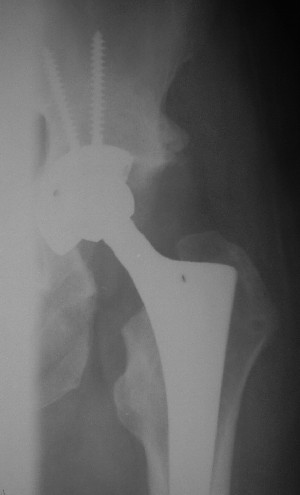

После протезирования прямой 5/04/04

|

Больной 18 мая 2003 года в автоаварии получил перелом левой вертлужной впадины, вывих бедра. Госпитализирован в один из стационаров области.Вывих вправлен. В последствии бедро вывихивалось еще дважды. На консультацию был представлен снимок от 19.05.03г., больной переведен к нам 3.06.03г. Снимок при поступлении - перелом впадины, задне-верхний вывих бедра. 05.06.2003 г. выполнено открытое вправление вывиха левого бедра и остеосинтез стенки вертлужной впадины двумя винтами. Послеоперационный период без осложнений. Объем движений в левом тазобедренном суставе восстановился полностью. Выписан на амбулаторное лечение в удовлетворительном состоянии с рекомендациями 3 месяца ходить на костылях без нагрузки на оперированную конечность. На контрольных рентгенограммах левого тазобедренного сустава 13.10.2003 г. - признаки консолидации перелома; плотность, форма головки и состояние суставных поверхностей удовлетворительные. Разрешена дозированная осевая нагрузка, на конечность с использованием дополнительной опоры. 19.12.2003 г. больной обратился с жалобами на боли в левом тазобедренном суставе. На рентгенограммах левого тазобедренного сустава 19.12.2003 г., 20.02.04г. - асептичекий некроз головки бедра. 5.04.04г. - эндопротез. Сейчас ходит без трости, не хромает. Особенность эндопротезирования - при удалении винтов прослежена линия перелома заднего края впадины и предложено установить чашку несколько меньшего диаметра, чтобы она была покрыта несломанной частью.